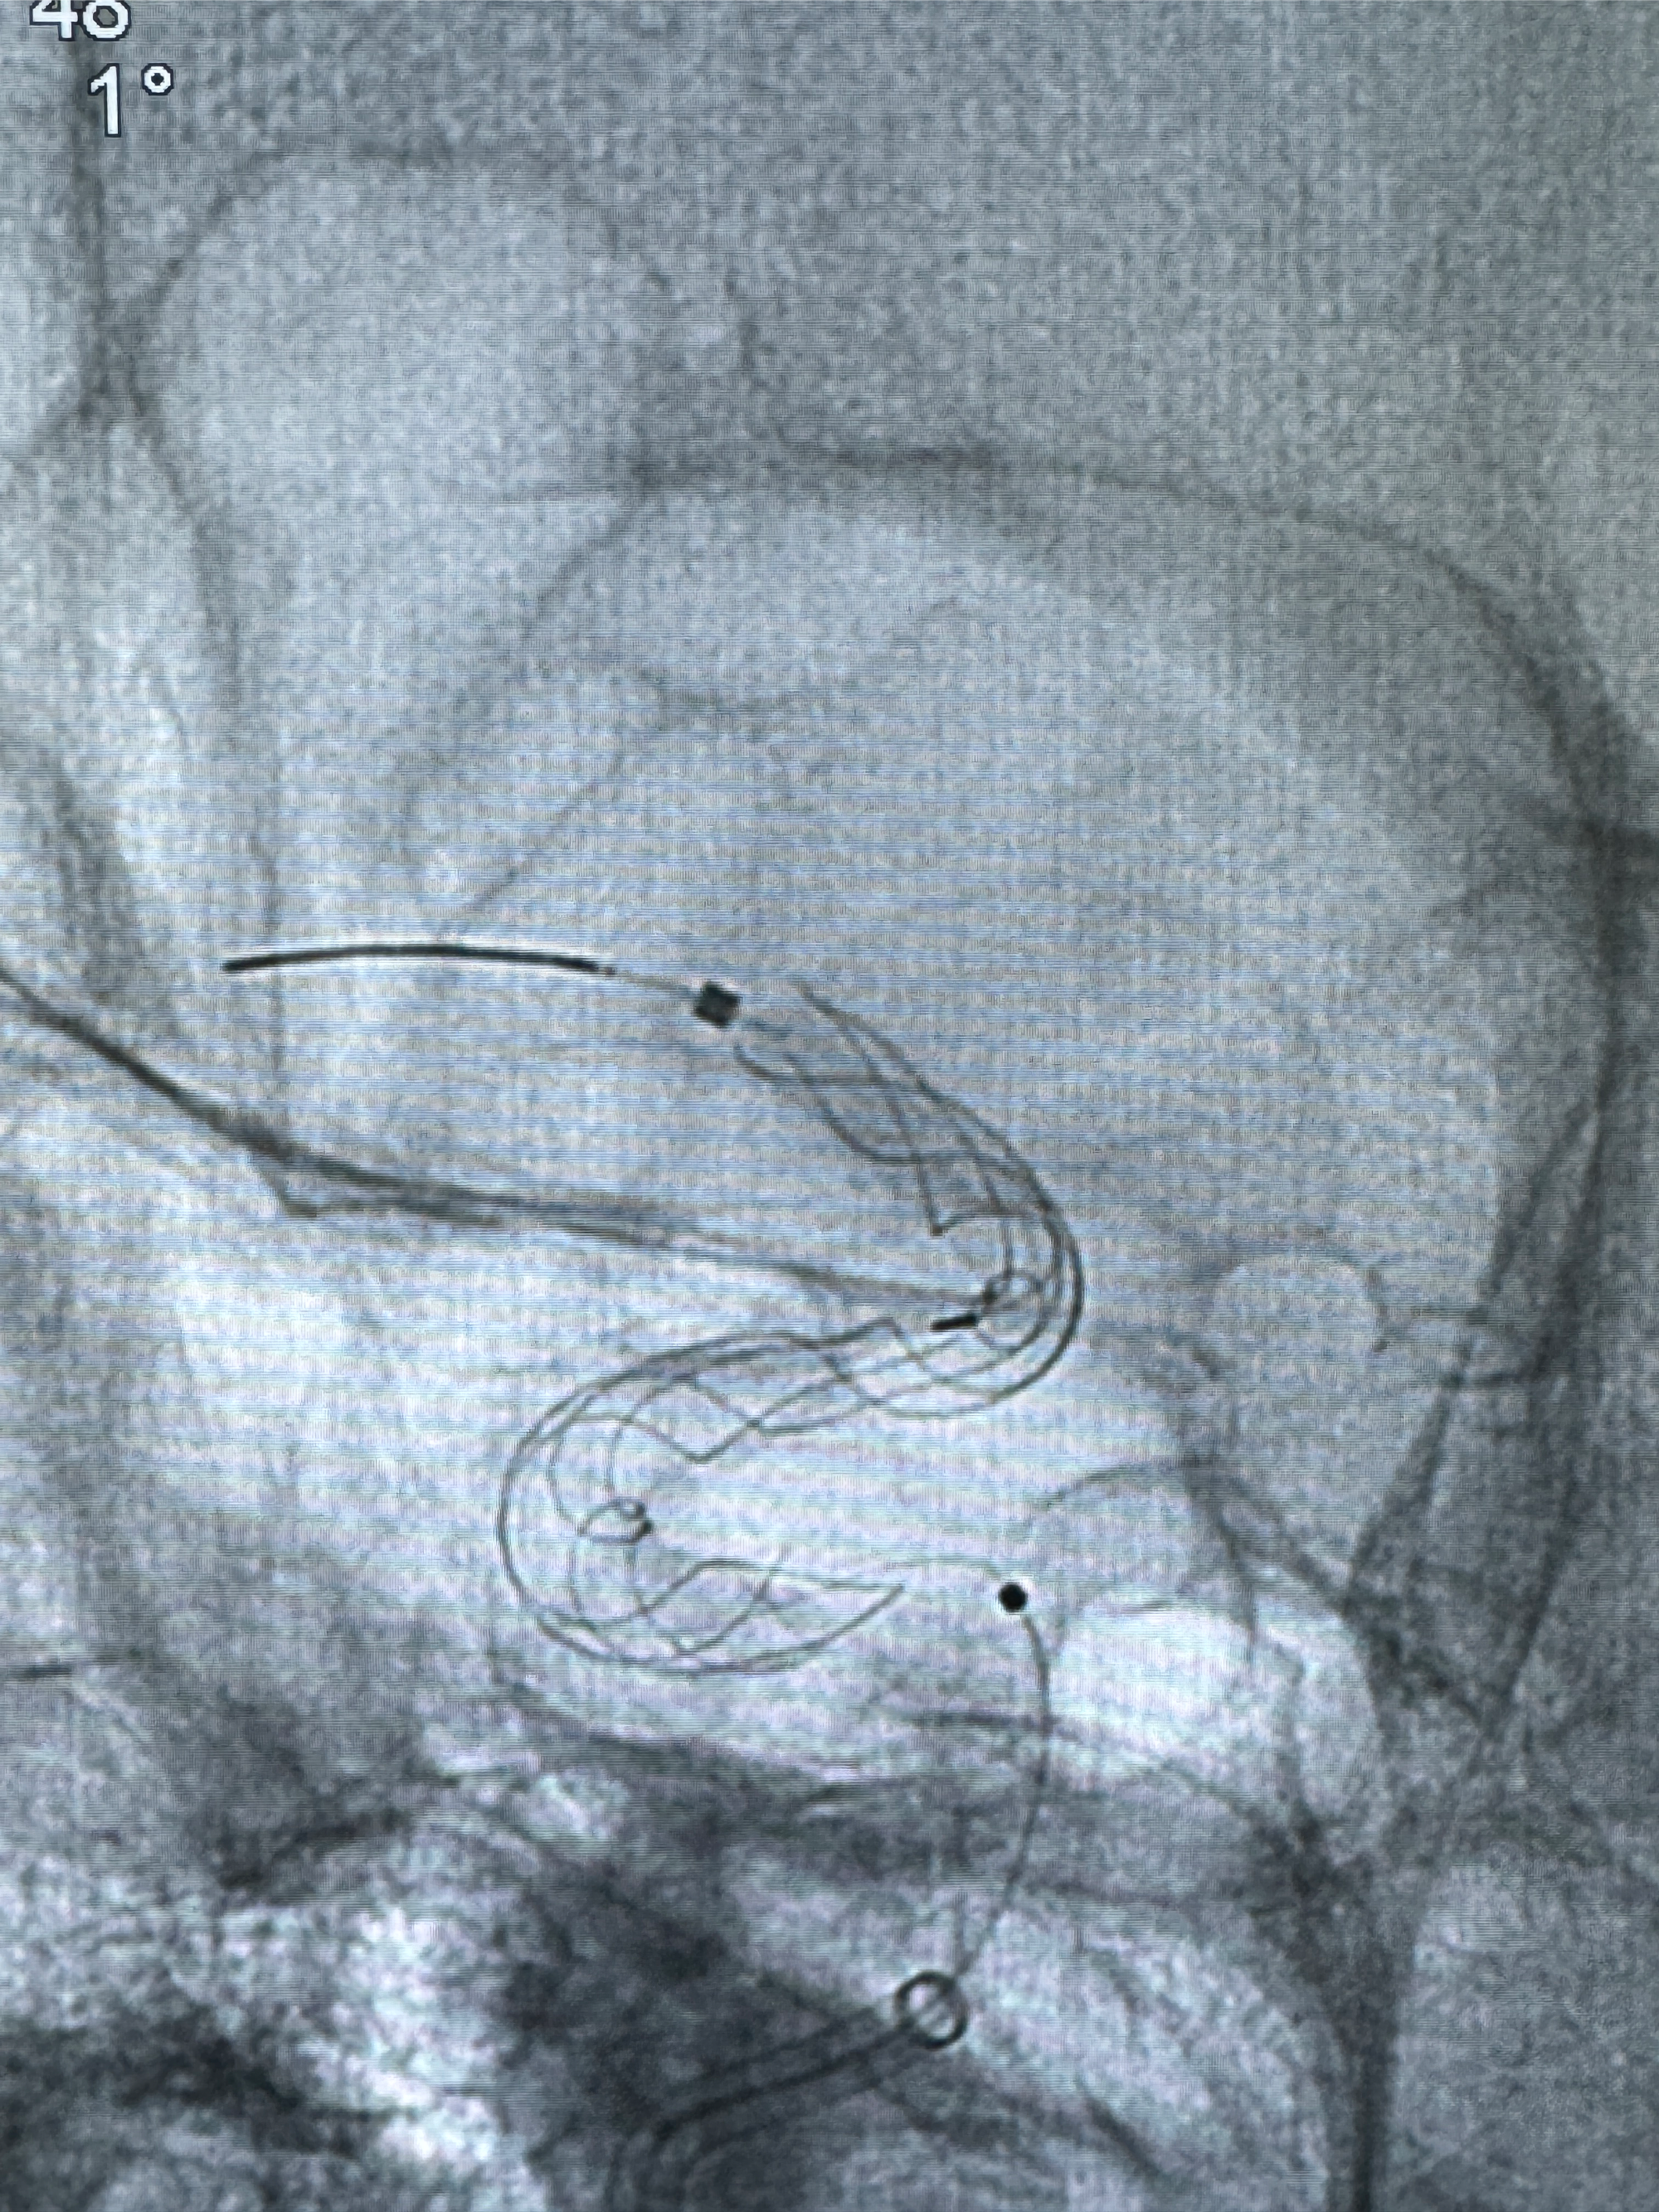

手术开始了,088导管在MPA及泥鳅导丝引导下进入右侧颈内动脉,灌注盐酸法舒地尔5mg

密网支架微导管在微导丝引导下超选择性插入右侧大脑中动脉

切换到动脉瘤瘤颈的角度,栓塞导管塑形后引入动脉瘤内

再次切换到动脉瘤远段血管支架释放角度,预备植入支架

4.5-30mmTurbridge密网支架,于M1近心端打开

透视下支架释放满意

多角度显示支架打开情况

造影显示支架贴壁情况

调整好角度,透视下推挤支架,使支架贴壁

再次造影确认支架贴壁情况

预备完全释放支架

透视可见红圈部分为支架导管的头端

手推冒烟显示支架位置及展开情况,箭头为支架导管的位置

尝试回收支架失败,只能考虑释放支架了

逐帧图像展示歪着脖子释放支架,旁边吩咐助手手机摄影、拍照留像(透视机不能留影像)